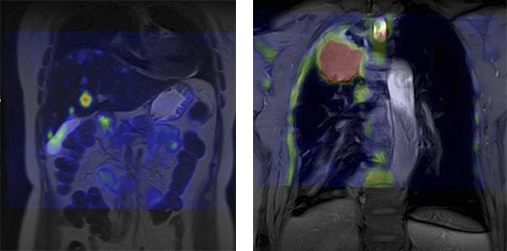

Спеціальне програмне забезпечення (Fusion) дозволяє зіставляти дифузно-зважені зображення (DWI) зі звичайними МР-зображеннями, дозволяючи точно локалізувати патологічний процес.

Отримані зображення відрізняються хорошим просторовим дозволом різних областей тіла і можуть бути порівняні із зображенням ПЕТ/КТ. Так, для пацієнтів, для яких неприйнятні стандартні методи дослідження з котрастом (КТ, МРТ, ПЕТ/КТ), DWI може стати методом вибору.